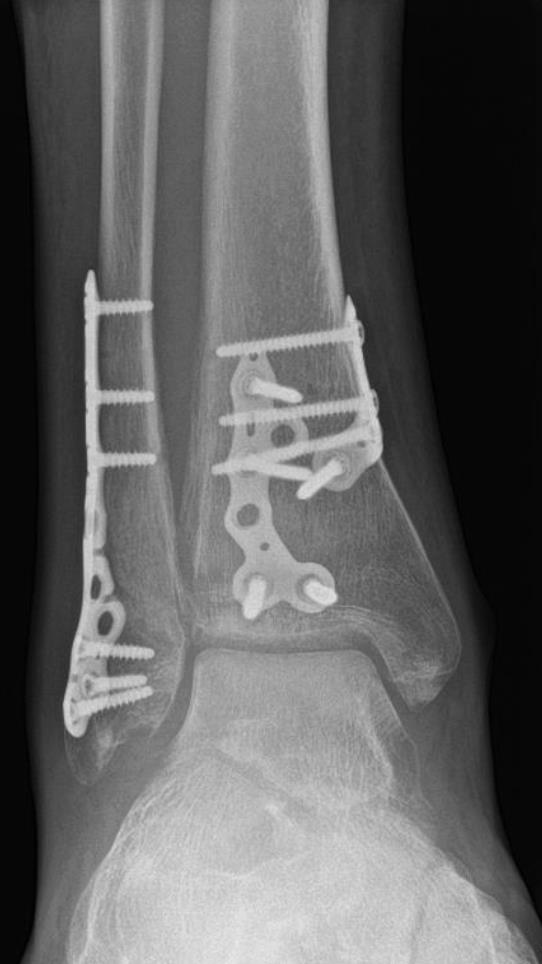

Volition® Ankle Fracture Plating

• VolitionTM Ankle Fracture Plates are available in six varieties: anatomic fibula plate, straight fibula plate, anatomic medial malleolar plate, posteromedial tibial plates (Type IIB), posterolateral tibial plates (Type IIA) and posterior tibial plates (Type III).

https://upload.orthobullets.com/topic/423287/images/bb0ba454-49e3-4c49-a225-2ffeaccefe04_2a-2b-volition-plate-x-ray..jpg